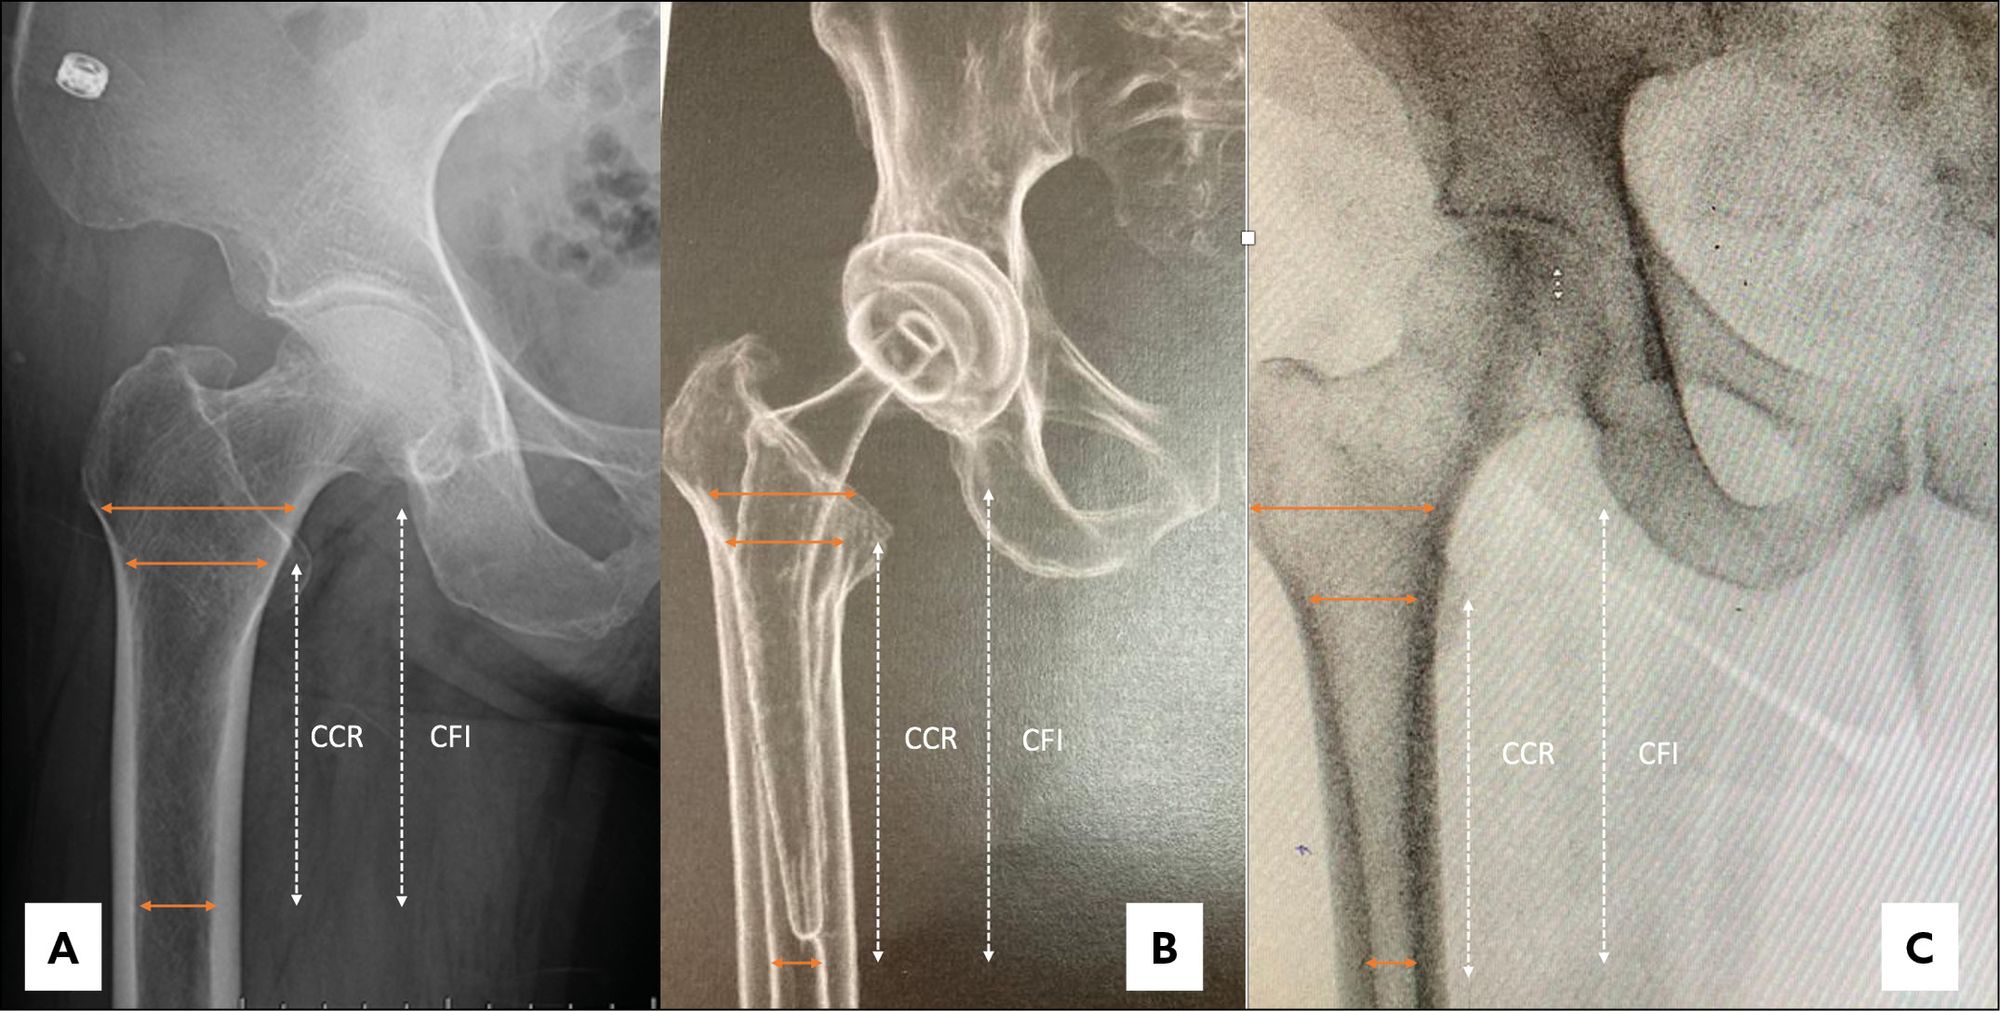

This issue's clinical contributions span alignment strategies and implant selection in major joint reconstruction. In total knee arthroplasty, one article examines TKA in extraarticular deformities managed through intraarticular correction without increased constraint, while a second introduces inverse kinematic alignment as a framework for personalized alignment. Shoulder arthroplasty is addressed through an assessment of the stemless shoulder implant. A further study evaluates whether surgical approach influences canal fill of the femoral component in THA, contributing to the evidence base on technique-dependent outcomes.